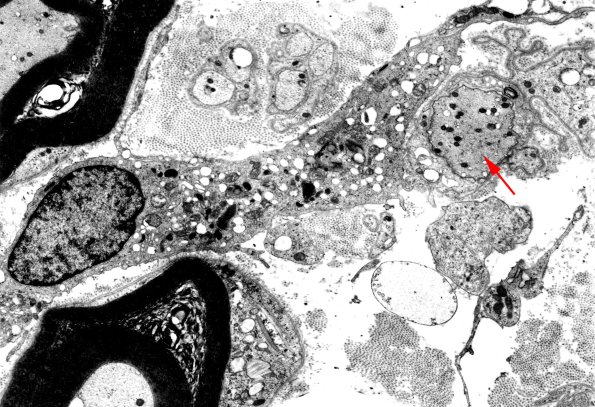

A macrophage containing myelin fragments and lipid droplets leaving the vicinity of a demyelinated axon (arrow).